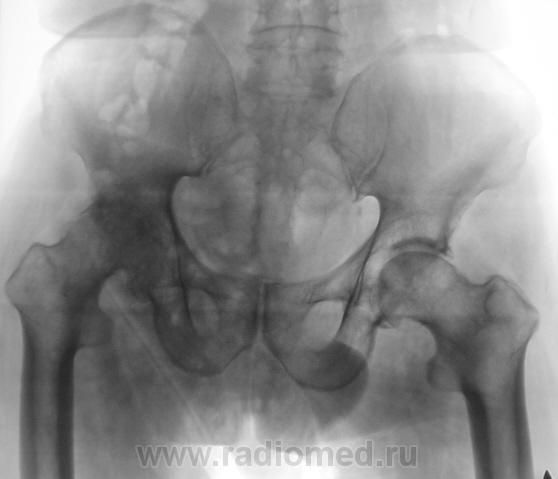

В принципе, болеть есть от чего. Однако, у меня на подозрении очаги разрежения структуры в головке левой бедренной кости и в теле правой подвздошной кости над вертлужной впадиной. Очаги весьма четкие, круглые - дообследуйте на предмет миеломной болезни.

Справа на фоне лонной и седалищной костей по-видимому тени кишки - грыжа?

Бластического варианта НЕТ. Очаги просветления, в данном случае -затемнения газ в к-ке. ДОА пр.т/б сустава 4 , левого - 2 степени, артрозные изм-я в сакроилеальных сочленениях, выраженней в левом

Правая половина таза меньше за счёт проекционного искажения?

Да, положение вынужденное.